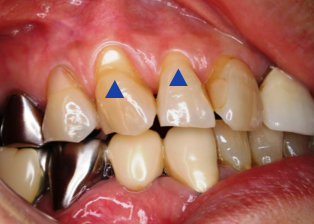

症例(歯肉移植による歯根面被覆)

誤ったブラッシングや歯ぎしり等により、歯茎(歯肉)が下がり、歯根面が露出してしまうことで知覚過敏が出現することがあります。この場合、露出した歯根面をカバーして知覚過敏に対処しますが、その方法の一つに歯肉移植による根面被覆術という方法があります。歯、歯肉の状況により適応にならない場合もありますが、審美性も回復することが可能な方法です。

治療の説明:歯ぐきが下がり歯の根が露出してしまっている部分に、歯ぐきを移植する治療法。見た目が改善されるだけでなく、知覚過敏や虫歯リスクの軽減にもつながります。